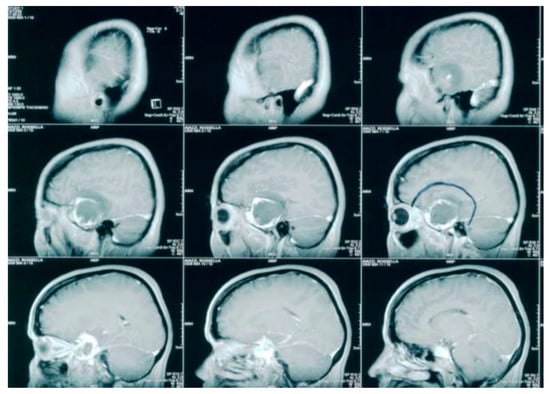

2. Case Presentation